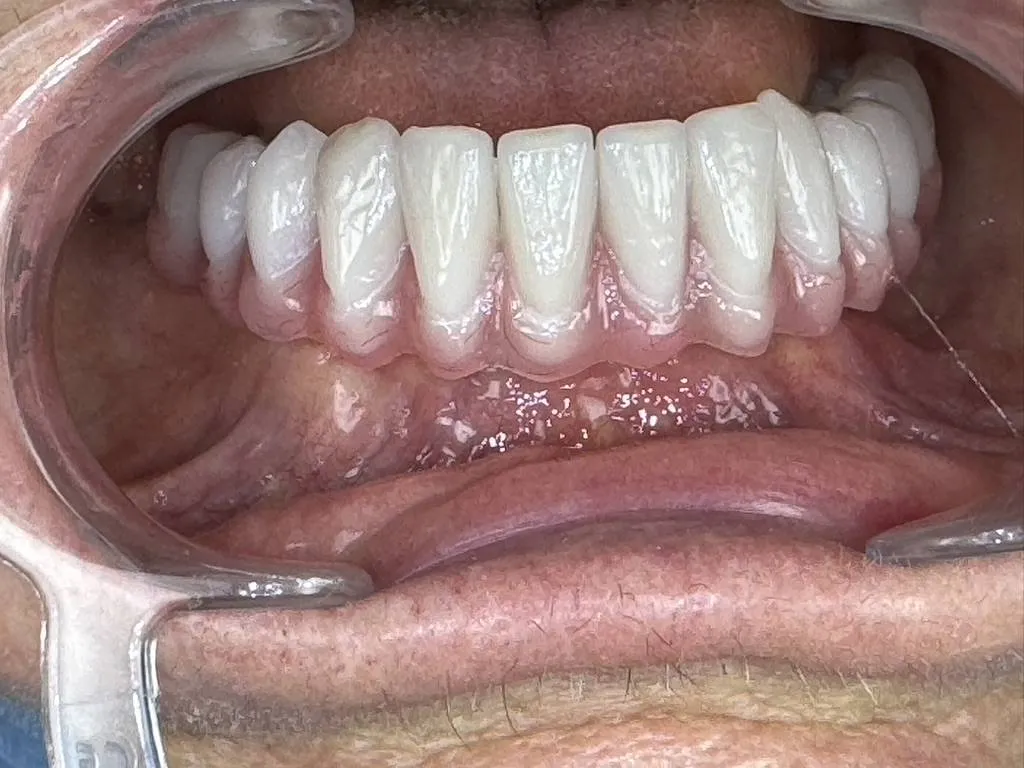

Cas de ALL ON 6 avec plastie osseuse pour corriger sourire gingival.Docteur Tourrolier didier.

la technique all on 6 permet de réhabiliter l’esthétique d'un sourire et de corriger des sourires gingivaux par une plastie osseuse.Explication du docteur didier Tourrolier spécialiste en implantologie dentaire.